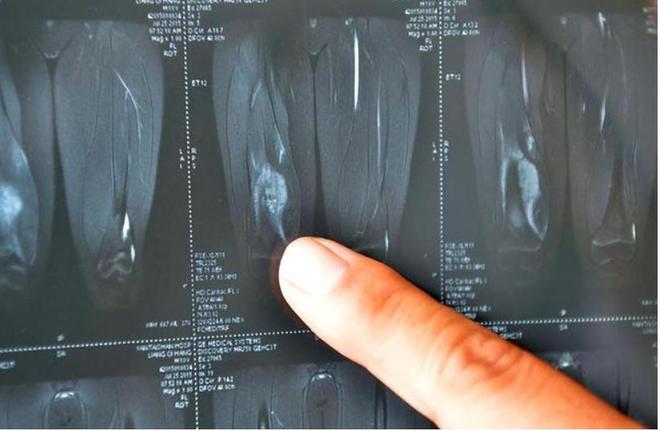

医生经过一番详细检查后,告诉李明馨和她的母亲:“你女儿的腿里发现了肿瘤,而且已经是恶性。”

为了确认诊断的准确性,李明馨的母亲带着她奔波于不同的医院,盼望着是误诊。